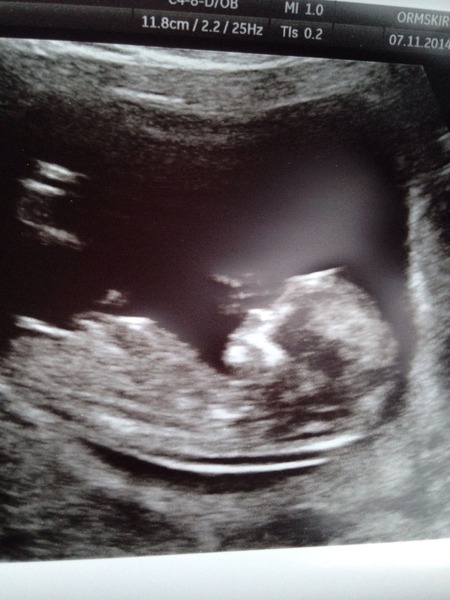

Fab picture snooky it must be lovely to tell your excited dc